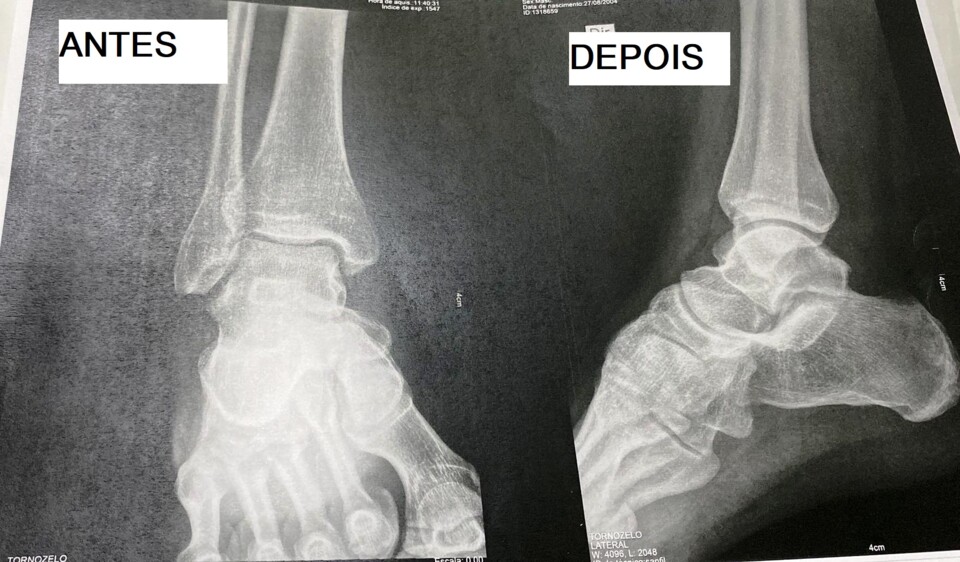

Não vou entrar em muitos pormenores, o RGPD não o permite, mas sabemos de fonte segura que um dos elementos dos PRETOSxBRANCOS recorreu a um serviço médico a fim de corrigir o desalinhamento dos pés - segundo os observadores experientes, ninguém pode jogar assim tão mal com pés normais, em desespero o individuo sujeitou-se à intervenção. Eis o resultado:

Os menos crentes nestas coisas irão perguntar-se: "Então e não corrigiu o pé esquerdo?" Calma, respondo eu - é só aguardar pelo reencontro dentro de campo com o Zé Rafael e o pé esquerdo ficará tão bom como este.

Brincadeiras à parte, o Grupo dos PRETOSxBRANCOS deseja a mais rápida recuperação ao Rafael Daniel.